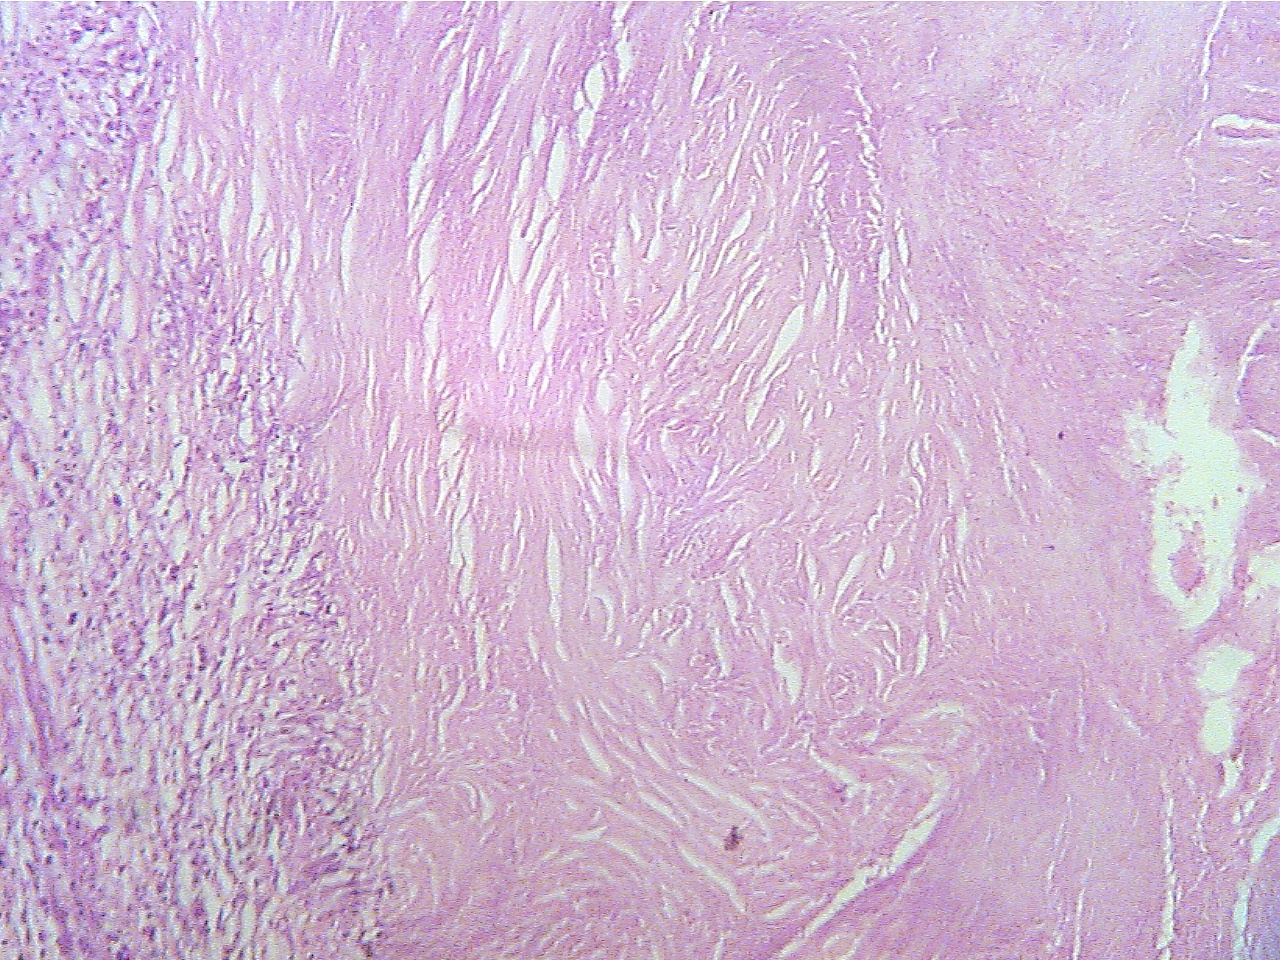

Ghon

tubercle (100X1.6)

Ghon tubercle (400X2.0)

Macrophages (left), fibrous capsule

(center), necrotic Macrophages

(round dark blue at left), fibrous capsule

region

(right)